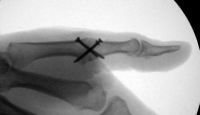

| In this case, 0.045"

K-wires were used for provisional fixation: |

| These were then replaced,

one at a time, with 1.5mm screws. Because of the entry angles, the

countersink bit was used to reduce screw head prominence. |